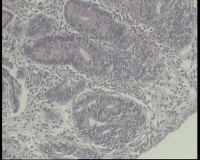

横结肠中部见一增生性肿物大小2.0x1.5厘米,表面糜烂充血,取材2块

2块组织内有1块正常,另一块局灶腺体异型,细胞复层排列,细胞核异型不太大,局灶够高级别吗?

高级别

局灶高级别。